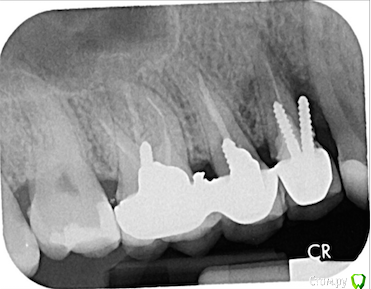

DmitrySH Опубликовано 27 сентября, 2016 Поделиться Опубликовано 27 сентября, 2016 (изменено) Это не импланты, а обычные анкерные штифты. 14 - перфорация корня, только удалять. И имплантировать.15 - тоже перфорация, но не так плохо. 16 -инородное тело в канале, очаг воспаления вокруг корней. Для понимания всей ситуации с зубами 16,15 желательно КТ Та смета, это удаление, имплантация и протезирование зуба 14. ( по их нумерации 5) Изменено 27 сентября, 2016 пользователем DmitrySH 2 Ссылка на комментарий